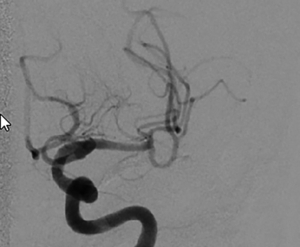

a) Verschluss der A. cerebri media links im M1-Segment | © C. Vockelmann

Der Eingriff erfolgt derzeit in der Regel in Intubationsnarkose, zunehmend auch in Analgosedierung in Intubationsbereitschaft, sollte sich der Patient klinisch verschlechtern. Auch hier gilt: Time is brain! Alle Abläufe sollten auf unnötige Handlungen überprüft und gestrafft werden. Für die Thrombektomie ist zunächst ein üblicher, steril gedeckter Angiografietisch erforderlich. Schleusenspülungen mit heparinisierter Kochsalzlösung (5.000 IE Heparin in 500 ml NaCl 0,9 %) müssen vorbereitet werden. Eine Kontrastmittelpumpe ist nicht unbedingt erforderlich, die Kontrastmittelgabe kann während der Intervention auch von Hand erfolgen. Der Zugang erfolgt über die rechte Leiste. Zunächst wird eine kurze 8F-Schleuse in der A. femoralis platziert. Hierüber wird eine 90 cm lange 6F-Schleuse oder ein 8F-Führungskatheter mit einem Vertebralis- oder Sidewinder-konfiguriertem Katheter und einem 0,035-inch-Führungsdraht in die ACI der betroffenen Seite vorgebracht. Jetzt erfolgt zunächst eine diagnostische Angiografie der intrakraniellen Gefäßstrombahn in 2 Ebenen. Sollte vor der Thrombektomie eine intravenöse Lysetherapie erfolgt sein, wird auf eine zusätzliche intraarterielle Heparingabe verzichtet, um das Blutungsrisiko nicht zu erhöhen. Für die Thrombektomie gibt es verschiedene Verfahren. Wichtiges Ziel aller Techniken ist neben der Wiederherstellung der Perfusion eine Vermeidung der Thrombusfragmentation mit Verschleppung in weiter distal gelegene Gefäßabschnitte oder auch neue, bisher nicht betroffene Gefäßterritorien.